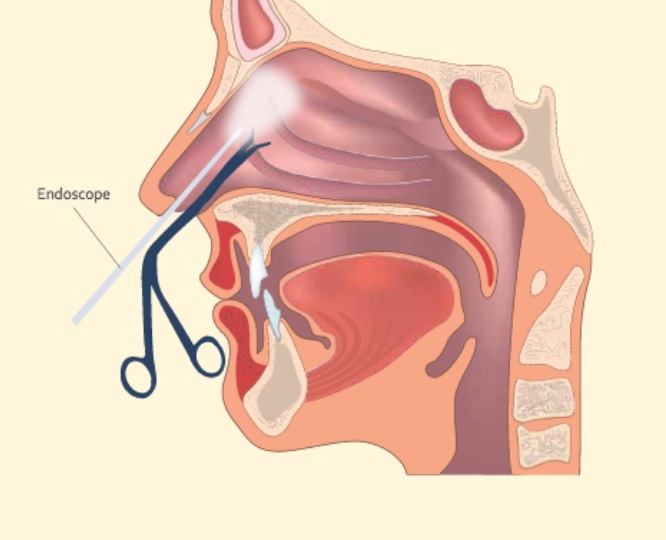

Overview

Package includes:

Days in hospital : 2 to 3 Days (For patient and one attendant)

Days in hotel : 7 Days (For patient and one attendant)

Room type in hospital : Shared

Room type in hotel : Private

Hotel category: Standard

Value added benefits of the FESS Bilateral: